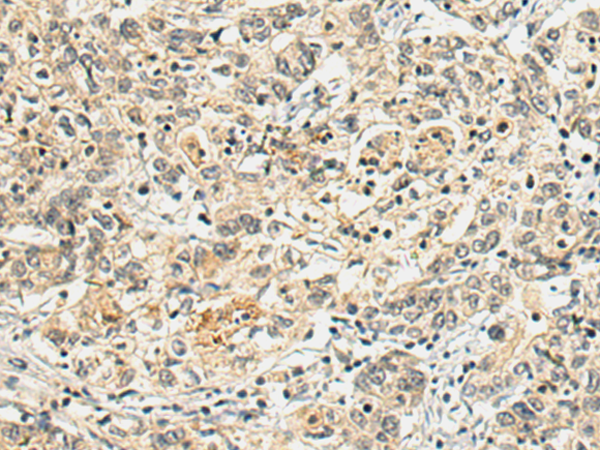

分类: 科研抗体货号: P13565别名: EULIR应用: IHC反应种属: Human, Mouse